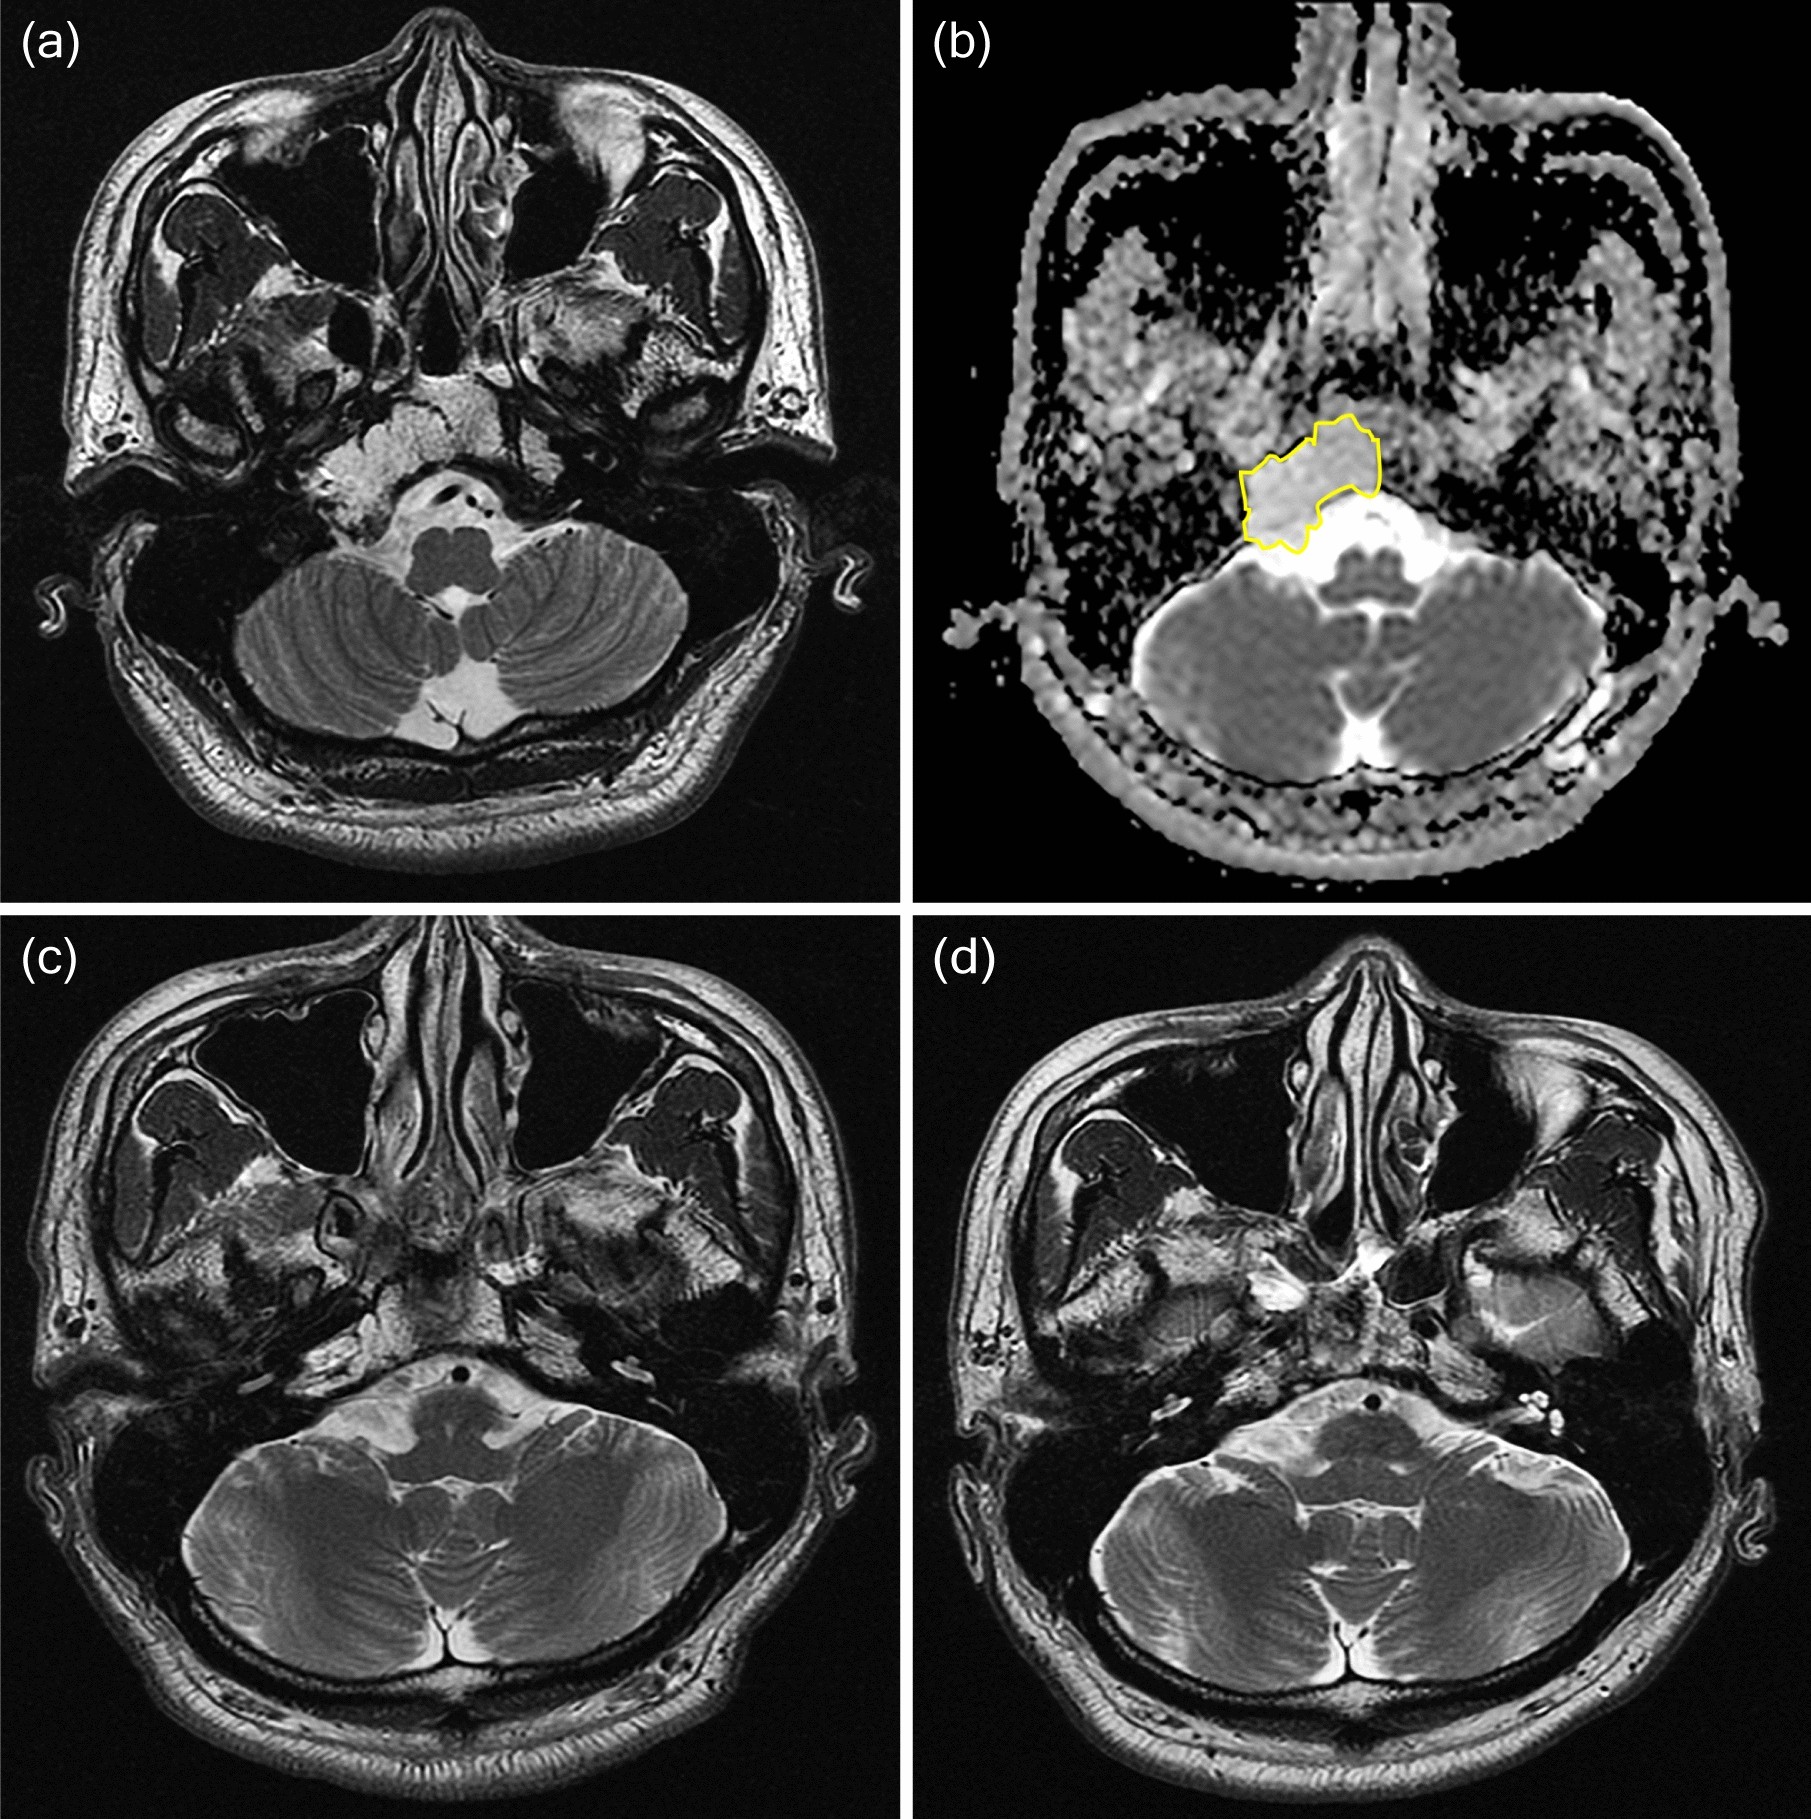

Figure 5

From: Apparent diffusion coefficient as a prognostic factor in clival chordoma

A 36-year-old man diagnosed with classic chordoma and placed in the stable group. (a) Preoperative T2-weighted imaging showed a T2 high signal mass arising from the clivus. (b) The ROI is outlined in yellow on the ADC map and represents moderate water diffusivity (mean ADC 1659 × 10–6 mm2/s, minimum ADC 1386 × 10–6 mm2/s). (c) Immediate postoperative T2-weighted imaging showed partial tumor removal. The operation was performed via the transsphenoidal approach. (d) T2-weighted follow-up imaging obtained 7 years later showed stable disease. The patient received conventional radiotherapy (62.5 Gy) 1 month after the first surgery.